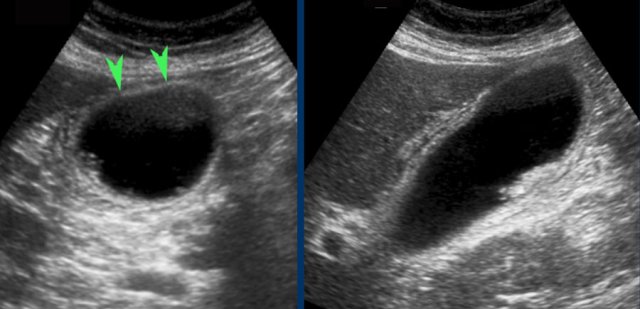

At day 0 there is acute hydrops due to an impacted stone.

One day later, the patient is symptom free.

The stone is still in place, but apparently allows passage of bile to the cystic duct, since hydrops has disappeared.

Reperfusion edema and sludge are the silent witnesses of the previous attack .

CRP remained normal.

Silent witness of previous attack.

US, performed 24 hours after colicky attack shows a contracted gallbladder with multiple small stones in patient who did not eat.

Seven days later the gallbladder is deployed again (visualized in again fasting patient).

Silent witnesses of a biliary colic in six different patient.

US was done 6-12 hours after the pain episode.

All patients were symptom free at the moment of US.